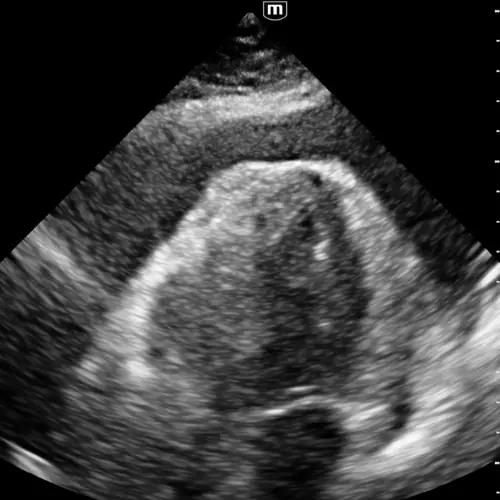

Épanchement péricardique et tamponnade

Le cœur piégé dans son propre sac